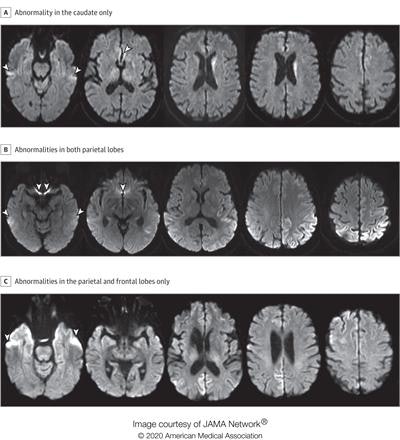

A: A man in his 70s with sCJD subtype VV2 with signal hyperintensity in the body of the left caudate, without evidence of signal abnormality in the putamina and neocortical ribbon. B: A woman in her 60s with sCJD subtype MM1 with signal hyperintensity in the cortical ribbon of both parietal lobes, left greater than right, and left precuneus without evidence of abnormality in the striatum, thalami, and cortical ribbon of the temporal and occipital lobes. C: A woman in her 70s with sCJD subtype MM1 with signal hyperintensity in the precuneus (right greater than left) and right parietal cortex. Images courtesy of JAMA Neurology.

A: A man in his 70s with sCJD subtype VV2 with signal hyperintensity in the body of the left caudate, without evidence of signal abnormality in the putamina and neocortical ribbon. B: A woman in her 60s with sCJD subtype MM1 with signal hyperintensity in the cortical ribbon of both parietal lobes, left greater than right, and left precuneus without evidence of abnormality in the striatum, thalami, and cortical ribbon of the temporal and occipital lobes. C: A woman in her 70s with sCJD subtype MM1 with signal hyperintensity in the precuneus (right greater than left) and right parietal cortex. Images courtesy of JAMA Neurology.The study included diffusion MRI scans from 872 patients. Of these, 619 had sCJD, 102 had other prion diseases, and 151 had nonprion disease. Four radiologists scored the MRI scans of 200 patients randomly selected from the pool of 872; of the 200, 150 had sCJD and 50 had nonprion diseases.